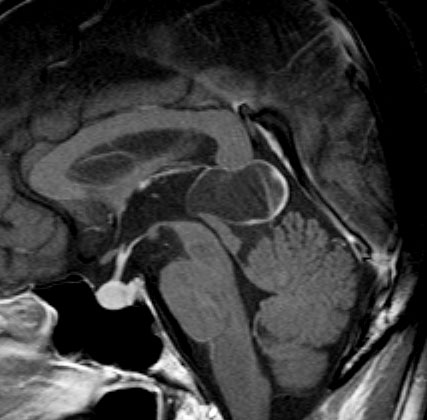

松果体細胞腫の例2(典型例)

成人女性の松果体細胞腫で充実性腫瘍です。多少凹凸がありますがだいたい楕円形。中脳水道が閉塞して軽度の水頭症(頭の中に髄液が溜まる)になってきています。急性水頭症で急変して意識障害になることがありますので,迷わず摘出するか,第3脳室開窓術 ETVをしてから経過観察します。